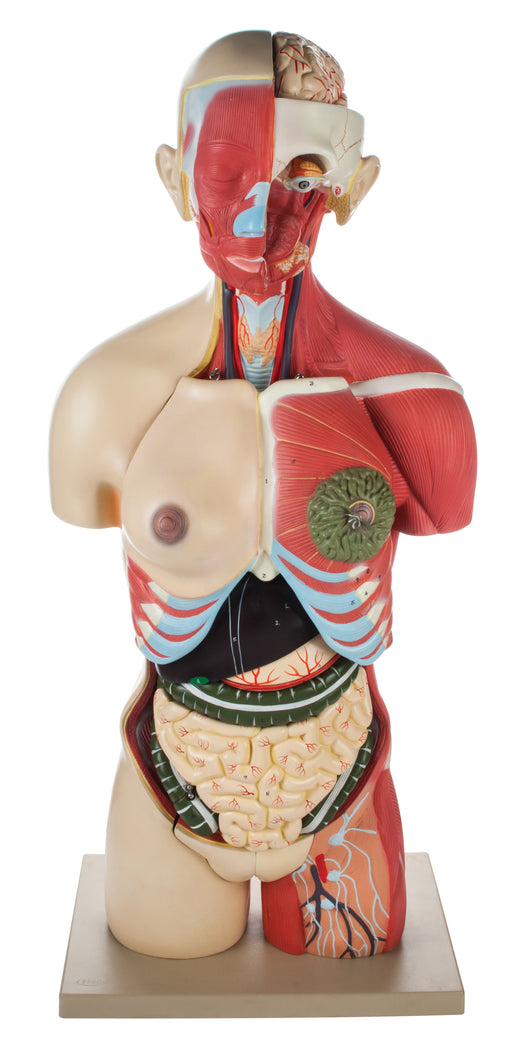

Full Muscular Torso Natural with Dual Sex Organs (30 Parts)

The detailed, life size 3D rendering of the human torso with its vibrantly colored anatomy is ideal for studying the structure and function of the ...

View full detailsAM16001 -